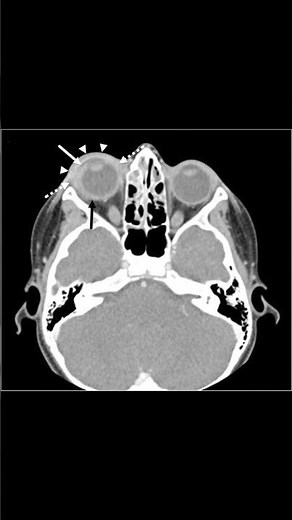

Radiopaedia - CT

Scan - Orbital